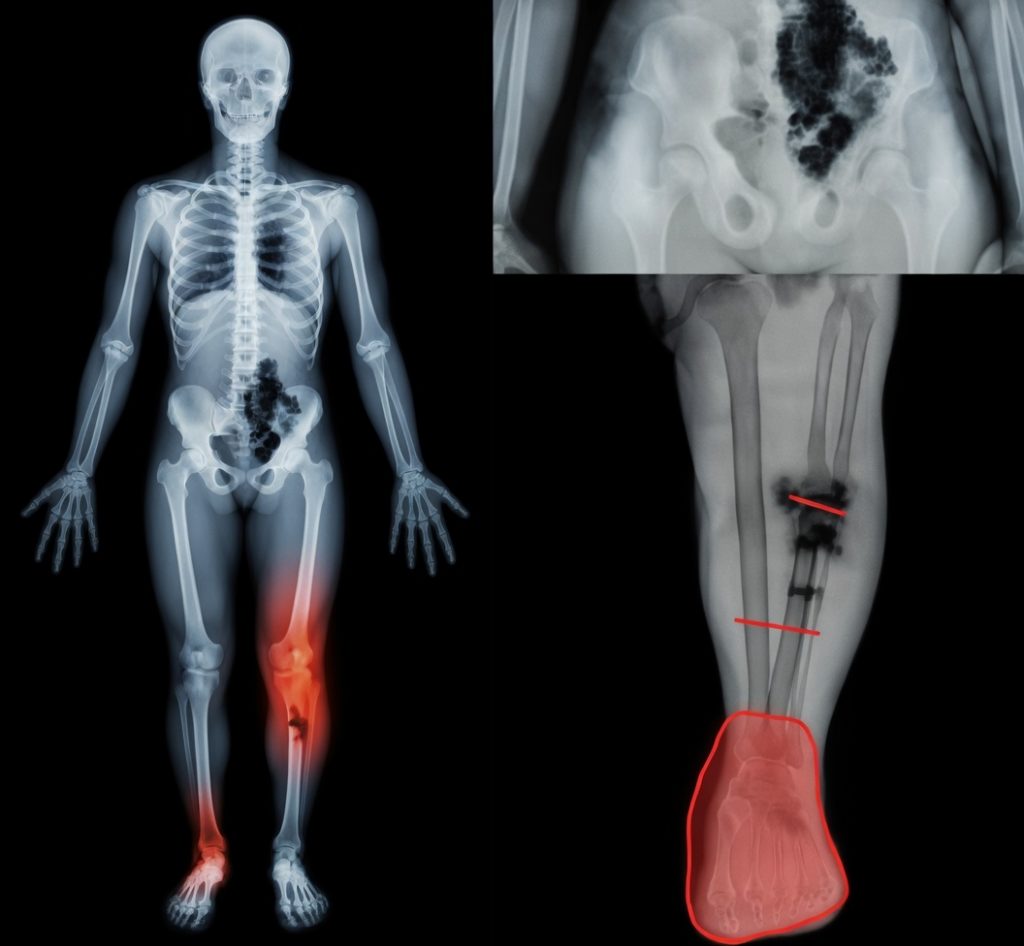

The first red flag is persistent fatigue that doesn’t match the person’s usual energy. It’s not just “getting old.” It’s often the immune system staying in low-grade overdrive, quietly taxing the heart, kidneys, and brain. Studies show up to 70% of seniors hospitalized for respiratory illness (flu, pneumonia, COVID) experience measurable muscle loss and reduced heart efficiency within 3–6 months — even if they never had heart problems before.

Heart and kidney strain are silent killers in this window. A bad respiratory infection can spike blood pressure and stress the heart muscle. Kidneys, already working harder with age, can take a hit from dehydration, antibiotics, or reduced blood flow during illness. The result: new or worsening hypertension, irregular rhythms, or creeping creatinine levels that show up months later.

Mobility and fall risk skyrocket. Muscle loss (sarcopenia) accelerates after just 7–10 days of bed rest or reduced activity. Balance worsens. Bone density drops faster. One study found seniors hospitalized for flu were 2.5 times more likely to fall and fracture a hip in the following year. Many families miss the connection — they think it’s just “getting older.”